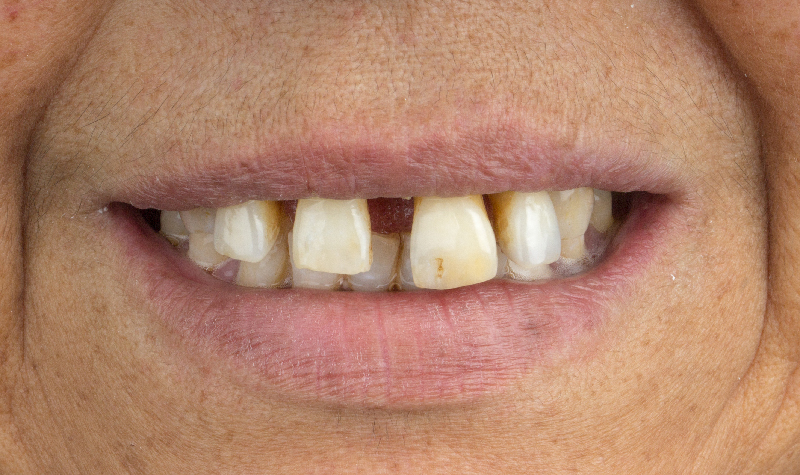

Rehabilitación oral total de alta complejidad con cerámicas sobre dientes e implantes.